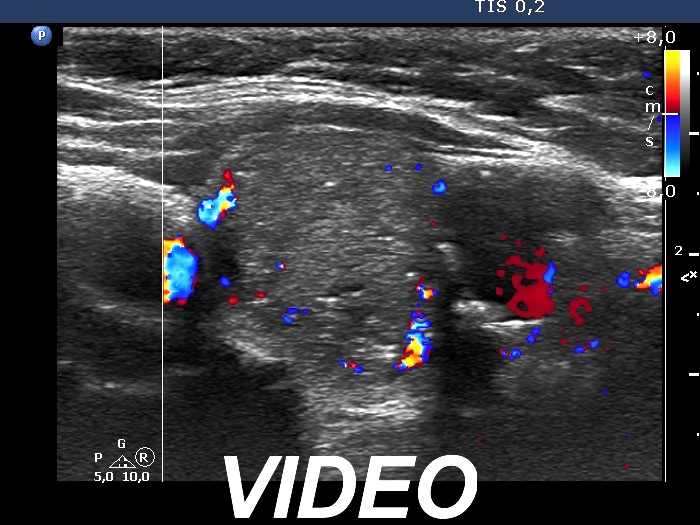

Second examination 7 years later (second and third rows of images):

Ultrasonography. The presentation remained unchanged. Using a better ultrasound device, it turned out that the echogenic granules are related to ventral cystic areas. Therefore, these are not microcalcifications, but figures caused by back wall cystic enhancement.Suggestion: yearly TSH determination, ultrasound in 4 years.

- The interpretation of the discrete lesions in the left lobe is difficult. I mean that this is a dominantly solitary nodule with a peripheral-type cystic portion. (See the explanation at the images.)